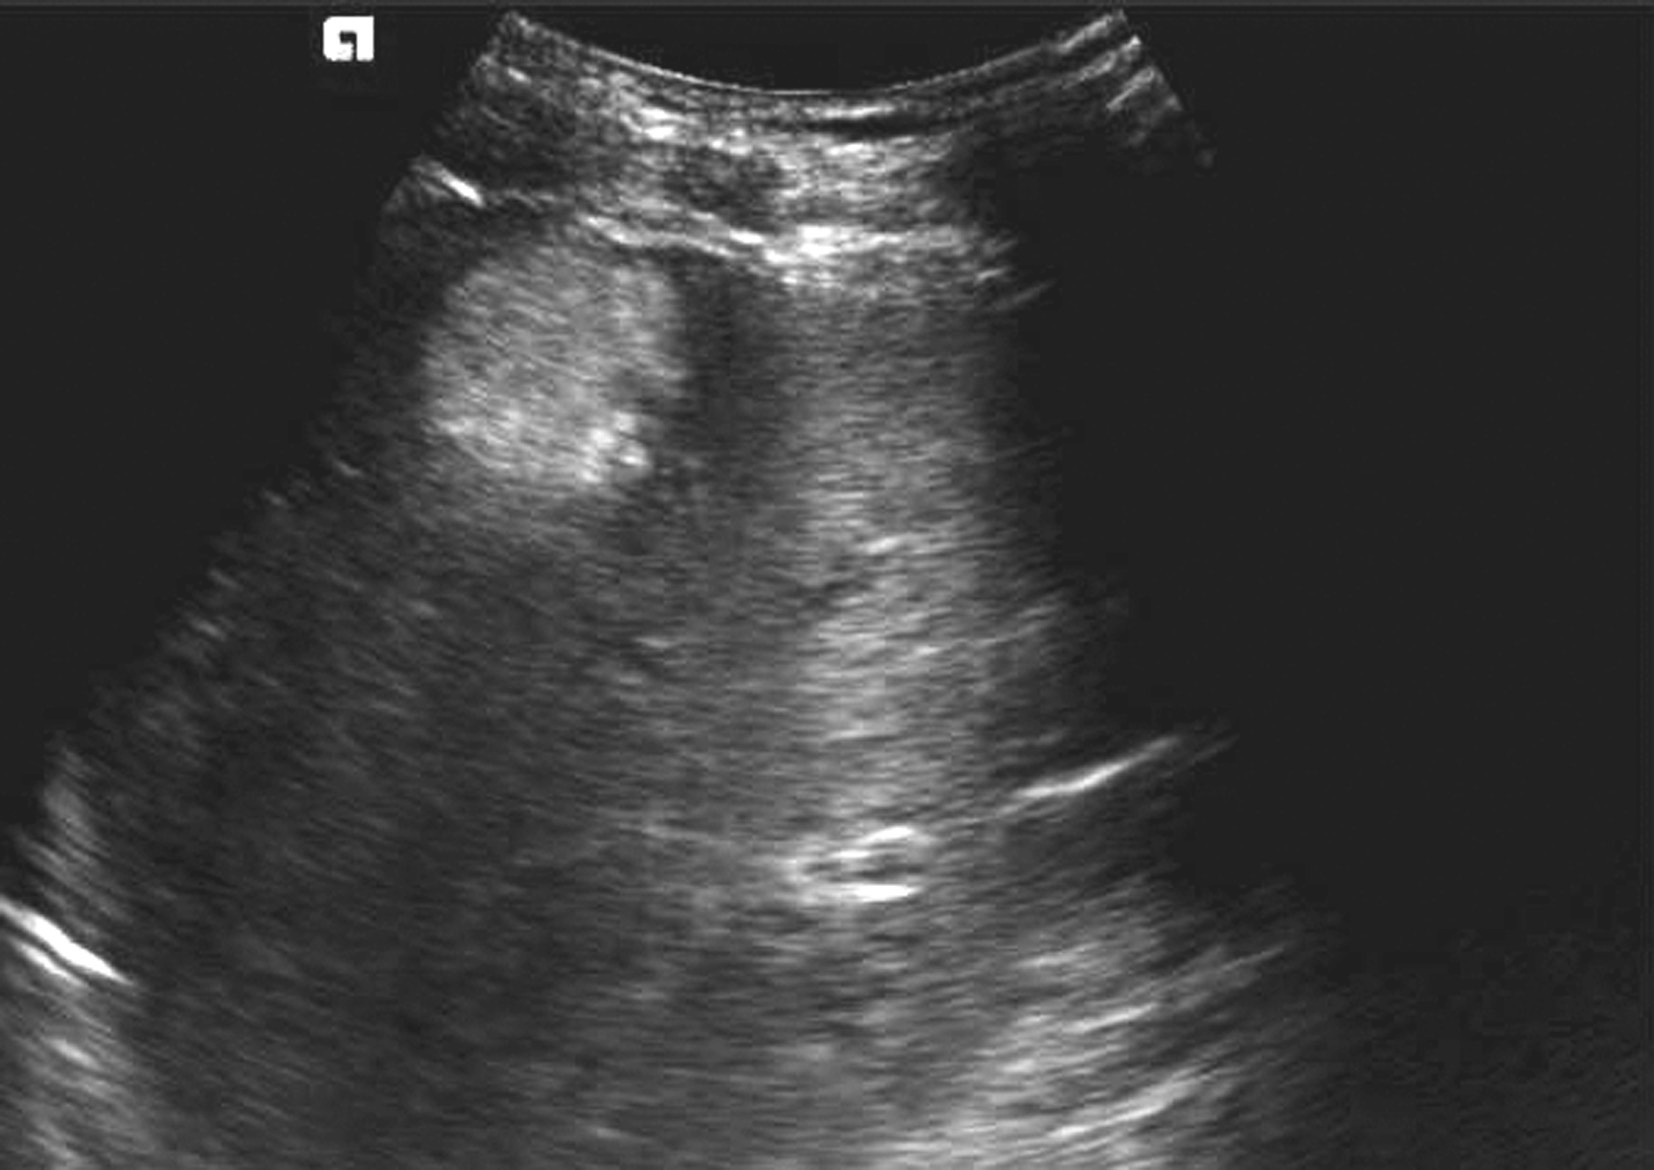

【声像图表现】

(1)肝细胞癌(hepatocellular carcinoma,HCC):

是肝脏最常见原发性恶性肿瘤,绝大部分病例与乙、丙型肝炎和肝硬化有关,占肝恶性肿瘤的80%~90%,男性多见,与乙肝和黄曲霉素相关,分为块状型、结节型、弥漫型及小癌型。在肝硬化的患者中,小的局灶性病变几乎代表着早期肝细胞癌或增生结节。小肝癌二维灰阶图像如图5-21-17所示。

图5-21-17 小肝癌二维灰阶图像

1)灰阶超声: